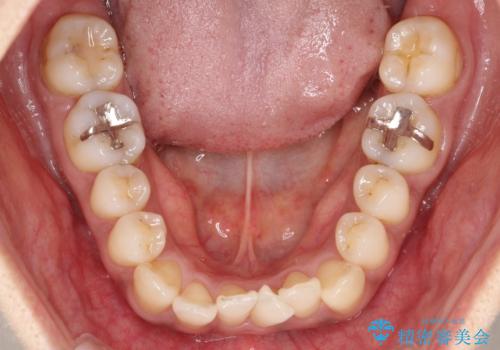

【審美装置】抜歯の本数最小限で行った矯正治療

- 審美装置

- 全体のがたつきを主訴に来院されました。4番目の歯を4本抜歯も検討しましたが、口元が下がりすぎてしまうリスクと2番目の転位うが著しく並べるのにかかる期間を考慮し、変則的な抜歯をし、並べる計画を立てました。

抜歯矯正のため2年はかかってしまいましたが、きれいに並び患者様にも満足頂きました。